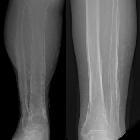

Periosteal reaction, also known as periostitis or periosteitis, is a nonspecific radiographic finding that indicates periosteal irritation. Periosteal reactions may be broadly characterized as benign or aggressive, or more specifically categorized by pattern.

Periosteal reaction may be classified as benign or aggressive (note: not benign and malignant) based on the time course of the initiating process.

Low-grade chronic irritation allows time for the formation of normal or near-normal cortex. The cortex will be thick and dense and have a wavy or uniform appearance.

Benign periosteal reactions can be seen in callus formation in a fracture or with slowly growing tumors.